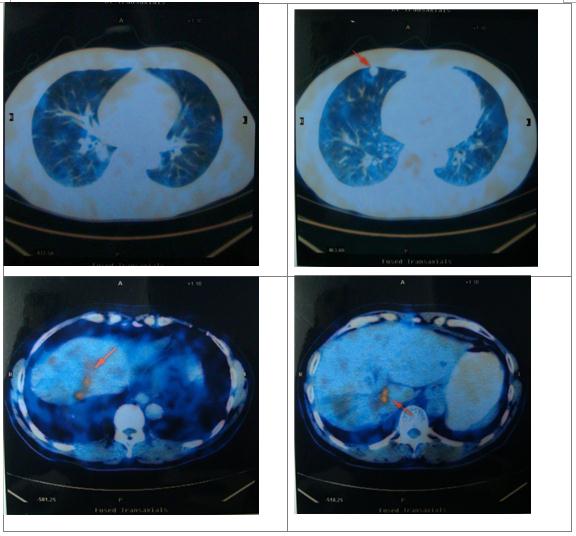

术后2月复查

复发治疗

复发时间:2016.2

4、复发后治疗是否应该考虑全身治疗联合局部治疗以控制疾病进展?

患者术前FOLFIRI+贝伐治疗有效,复发后可以继续该方案治疗。患者肝、肺复发病灶较小,是否能联合局部治疗以清除病灶、延缓疾病进展,减少后续化疗负担。NCCN指南推荐消融技术可单独应用或与切除相结合,所有病变部位均需行消融或手术。对于化疗耐药或难治的肝转移为主的患者,在严格选择患者情况下,可应用动脉插管治疗,特别是钇90微球动脉栓塞疗法。

该患者在术后约半年时间出现了右肺和肝脏新发病灶,左肺可疑病灶,可考虑再引入FOLFIRI联合贝伐单抗的治疗,若疗效评价为SD或PD,应行多学科专家团队(MDT)讨论,让肝胆外科、胸部外科、介入科和放疗科医生共同讨论是否可针对其新发病灶进行治疗。另外,该患者父亲也患有结肠癌,应仔细询问其发病年龄和家族是否有其他肿瘤患者。按照中山大学肿瘤医院Lynch综合征分子筛查流程,其MMR蛋白表达正常,若符合Bethesda标准推荐进行MSI检测,若MSI-H还应该再检测MLH1甲基化或BRAF突变,若两者皆阴性建议其进行MMR基因胚系突变检测以鉴别是否Lynch综合征。

一线治疗以肿瘤退缩为目的争取手术根治机会应推荐有效率更高的方案;二线治疗取得有效后停药时间过长应在停用贝伐单抗准备手术的基础上再行化疗两到三程;化疗配合根治性手术达到无疾病证据(NED)状态,围手术期化疗建议能达到半年时间;患者出现疾病复发后建议更加积极地进行多学科讨论采取多学科联合的方案。